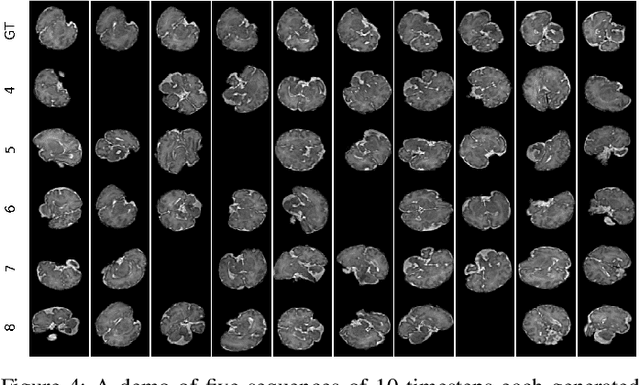

Abstract:Fetal magnetic resonance imaging (MRI) is challenged by uncontrollable, large, and irregular fetal movements. Fetal MRI is performed in a fully interactive manner in which a technologist monitors motion to prescribe slices in right angles with respect to the anatomy of interest. Current practice involves repeated acquisitions to ensure diagnostic-quality images are acquired; and the scans are retrospectively registered slice-by-slice to reconstruct 3D images. Nonetheless, manual monitoring of 3D fetal motion based on displayed 2D slices and navigation at the level of stacks-of-slices (instead of slices) is sub-optimal and inefficient. The current process is highly operator-dependent, requires extensive training, and significantly increases the length of fetal MRI scans which makes them difficult for pregnant women, and costly. With that motivation, we presented a new real-time image-based motion tracking technique in MRI using deep learning that can significantly improve state of the art. Through a combination of spatial and temporal encoder-decoder networks, our system learns to predict 3D pose of the fetal head based on dynamics of motion inferred directly from sequences of acquired slices. Compared to recent works that estimate static 3D pose of the subject from slices, our method learns to predict dynamics of 3D motion. We compared our trained network on held-out test sets (including data with different characteristics, e.g. different age ranges, and motion trajectories recorded from volunteer subjects) with networks designed for estimation as well as methods adopted to make predictions. The results of all estimation and prediction tasks show that we achieved reliable motion tracking in fetal MRI. This technique can be augmented with deep learning based fast anatomy detection, segmentation, and image registration techniques to build real-time motion tracking and navigation systems.

Abstract:Brain segmentation is a fundamental first step in neuroimage analysis. In the case of fetal MRI, it is particularly challenging and important due to the arbitrary orientation of the fetus, organs that surround the fetal head, and intermittent fetal motion. Several promising methods have been proposed but are limited in their performance in challenging cases and in real-time segmentation. We aimed to develop a fully automatic segmentation method that independently segments sections of the fetal brain in 2D fetal MRI slices in real-time. To this end, we developed and evaluated a deep fully convolutional neural network based on 2D U-net and autocontext, and compared it to two alternative fast methods based on 1) a voxelwise fully convolutional network and 2) a method based on SIFT features, random forest and conditional random field. We trained the networks with manual brain masks on 250 stacks of training images, and tested on 17 stacks of normal fetal brain images as well as 18 stacks of extremely challenging cases based on extreme motion, noise, and severely abnormal brain shape. Experimental results show that our U-net approach outperformed the other methods and achieved average Dice metrics of 96.52% and 78.83% in the normal and challenging test sets, respectively. With an unprecedented performance and a test run time of about 1 second, our network can be used to segment the fetal brain in real-time while fetal MRI slices are being acquired. This can enable real-time motion tracking, motion detection, and 3D reconstruction of fetal brain MRI.